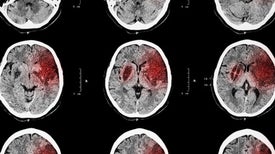

Shutting down an inflammatory molecule could potentially provide treatment days after onset